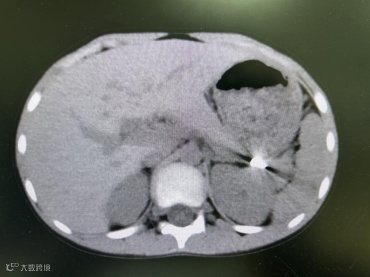

一场快乐的户外游玩,因一次攀高不慎戛然而止。10月13日下午,8岁的小金(化名)在攀爬高处时不慎摔下,因为没有明显外伤,所以当时家长只是带回家观察,并未做特殊处理,直到晚上小金说左侧肋部疼痛越来越剧烈,家长这才匆忙将他送来北海市第二人民医院急诊就医。经验丰富的急诊医生觉察到,小金大概率有内伤!CT检查结果揪紧了所有人的心:脾破裂并出血。

造影脾动脉栓塞以远动脉显影减少,血流速度明显减慢,远端动脉分支造影剂外渗明显减少。

经过后续的精心治疗与观察,患儿目前已恢复良好得以出院。他保住的不仅是一个器官,更是一个无忧无虑、健康完整的童年。

出院后10天复查情况良好